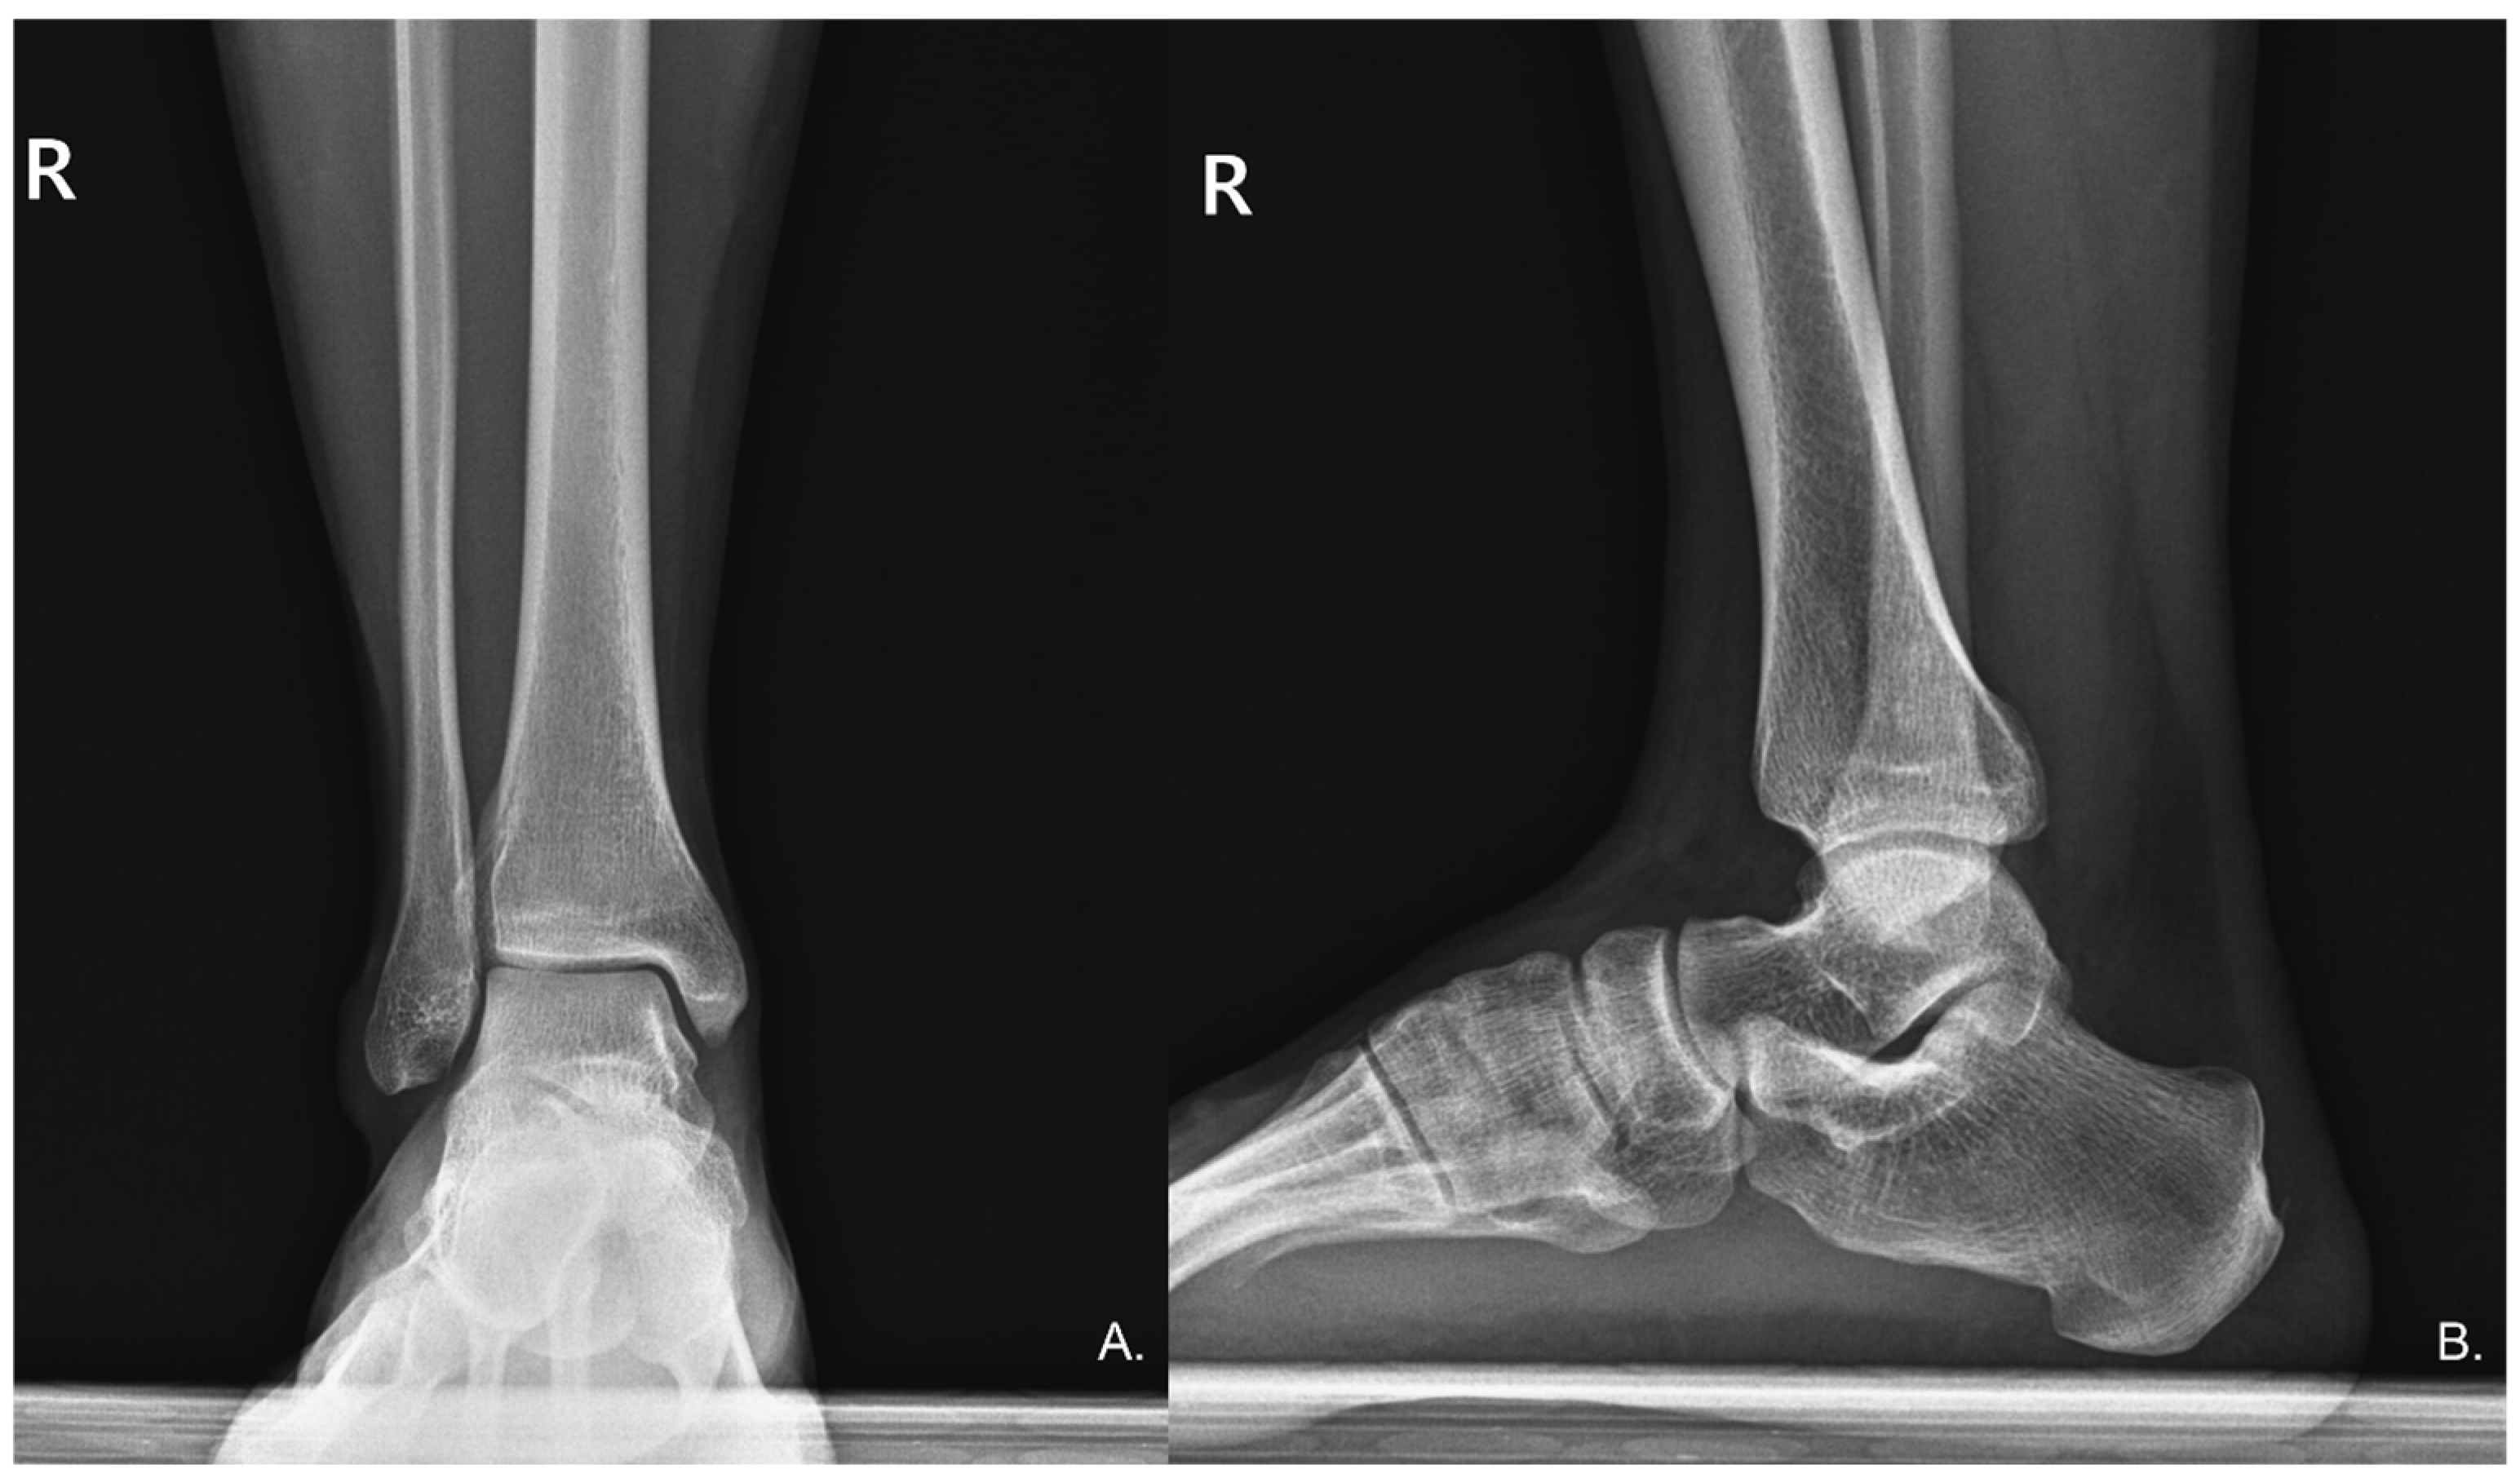

Figure 2.

(A) Anteroposterior (AP) and (B) Lateral radiographs of the right ankle show no radiographic evidence of deformities or other significant bony abnormalities.

Physical examination revealed an antalgic gait during ambulation to the consultation area. Palpation elicited significant tenderness in the posterior calcaneal region, with passive dorsiflexion of the right ankle provoking substantial discomfort. A well-demarcated psoriatic plaque was observed on the right calf (Figure 1), correlating with the patient’s six-year history of psoriasis for which no active treatment was being administered. Neuromuscular assessment demonstrated decreased pin-prick sensation in the sural nerve distribution distal to the psoriatic plaque. A Tinel’s sign was positive, with percussion over the psoriatic plaque eliciting concordant paresthesias radiating distally along the anticipating pathway of the sural nerve. The remainder of the comprehensive neurological evaluation of the lower limbs yielded unremarkable findings. Standard anteroposterior and lateral radiographs of the ankle revealed no structural abnormalities (Figure 2).